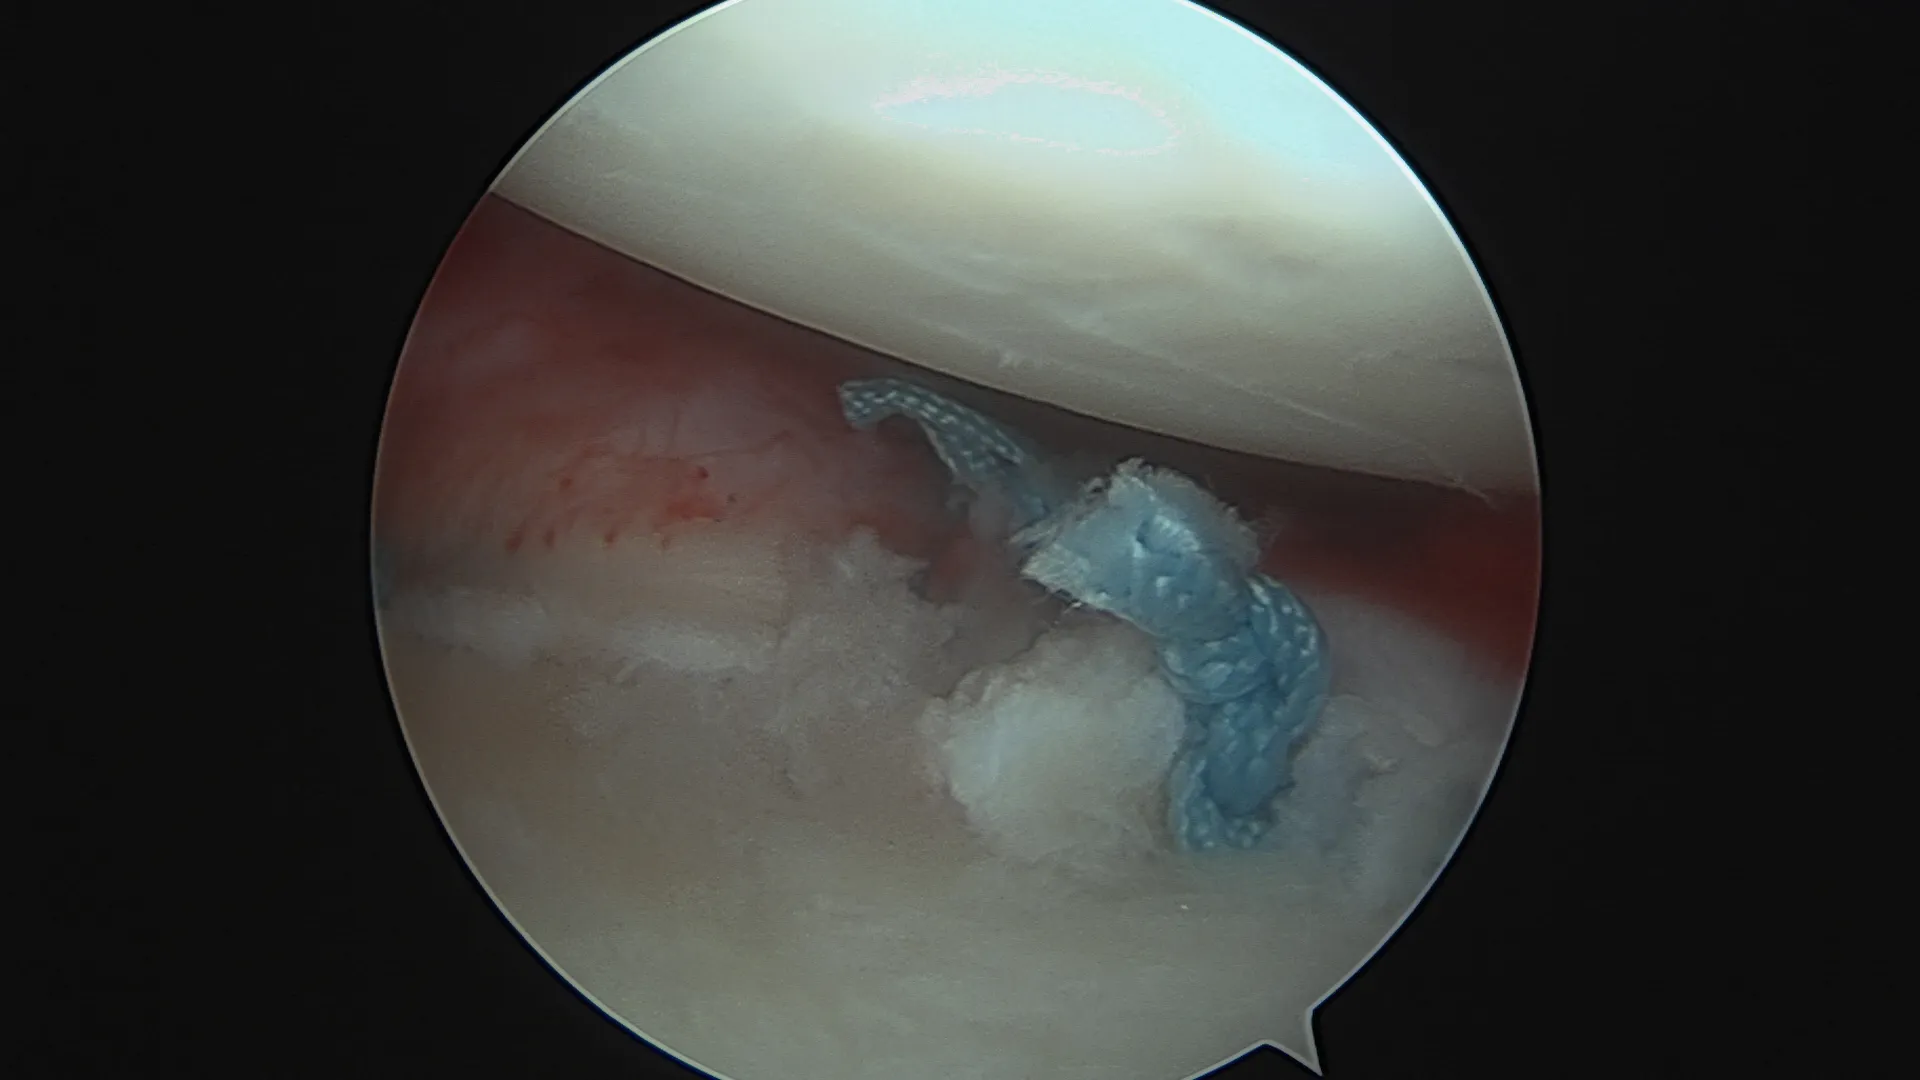

Réparation de Bankart — sous arthroscopie

Comment ? L'intervention est réalisée entièrement sous arthroscopie (vidéochirurgie), par 2 à 3 incisions de quelques millimètres seulement. Le labrum arraché est réinséré sur la glène à l'aide d'ancres résorbables sur lesquelles sont fixés des fils très résistants. Les ligaments gléno-huméraux distendus sont retendus dans le même temps opératoire.

Résultat : taux de succès élevé dans les indications bien posées. Reprise sport sans contact vers 4 mois. Non indiqué en première intention pour les sports de contact ou d'armé-contré.

Le remplissage de l'encoche postérieure (Hill-Sachs remplissage)

Pour qui ? En complément du Bankart, quand l'encoche humérale postérieure est engageante.

Comment ? L'encoche est comblée en plicaturant la coiffe des rotateurs dans le défect osseux à l'aide d'ancres miniaturisées. Cette technique arthroscopique évite dans certains cas de recourir à une butée.